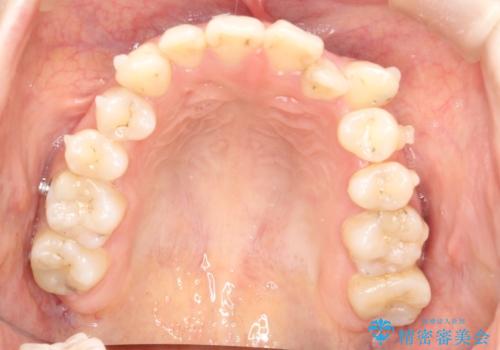

八重歯をインビザラインで非抜歯矯正

- 八重歯を主訴に来院されました。

インビザラインにて奥歯を後方に移動して八重歯が入るスペースを確保してく矯正する計画としました。

八重歯と前歯のガタガタがなくなり、歯並びがきれいになったのと、かみ合わせも改善することができました。